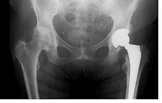

Wybór techniki znieczulenia u osób poddawanych wymianie stawu biodrowego jest nadal dyskusyjny. Założeniem tego badania było udowodnienie, że znieczulenie ogólne niesie za sobą więcej korzyści w bezpośrednim okresie po znieczuleniu niż blokada rdzeniowa.

więcejCałkowite znieczulenie dożylne versus znieczulenie podpajęczynówkowe do zabiegu wymiany stawu biodrowego, kontrolowane badanie z randomizacją.